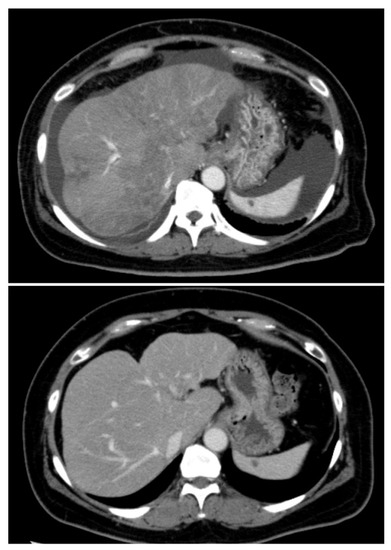

Primary adrenal lymphoma (PAL) is a rare entity that presents as unilateral or bilateral rapidly growing adrenal masses, with signs and symptoms most commonly related to adrenal insufficiency due to the mass effect on the surrounding tissues. Although steroeidogenesis has not been previously [...] Read more.

Primary adrenal lymphoma (PAL) is a rare entity that presents as unilateral or bilateral rapidly growing adrenal masses, with signs and symptoms most commonly related to adrenal insufficiency due to the mass effect on the surrounding tissues. Although steroeidogenesis has not been previously described in PAL, we herein report two cases of PAL presenting as adrenal incidentalomas (AIs) that demonstrated autonomous cortisol production. A 52-year-old woman presented with lumbar pain; a computed tomography (CT) scan demonstrated a left AI measuring 8.5 × 15 × 10 cm. Similarly, an 80-year-old woman presented with lumbar pain, demonstrating in a CT scan a bilateral AI (right: 9 × 6.5 cm, left: 3.6 × 3.2 cm). Both cases underwent a full hormonal evaluation according to the algorithm for the investigation of AIs, demonstrating increased 24-h cortisol excretion, suppressed fasting adrenocorticotropic hormone (ACTH) levels, and non-suppressed serum cortisol levels in both the overnight and the low-dose dexamethasone suppression tests, indicating autonomous cortisol secretion and Cushing’s syndrome. In a relatively short time, both patients developed night sweats, and their clinical picture deteriorated, while the CT scans showed increased dimensions of the masses with radiological characteristics compatible to lymphoma. Both patients underwent ultrasound-guided biopsies (FNBs), revealing infiltration of the left adrenal by diffuse large B-cell lymphoma in the first case, whereas bilateral adrenal infiltration from the same histological type was noted in the second case. Subsequently, they were treated with immunochemotherapy, but the second patient died from an infection shortly after the initiation of the treatment. To our knowledge, this is the first report of PAL presenting with Cushing’s syndrome due to autonomous cortisol production, indicating that neoplastic lymphoid cells in PAL might acquire the potential for steroidogenesis; therefore, more cases of PAL should be analyzed so as to further elucidate the complex pathogenesis and the natural course of this entity. Full article

Figure 1